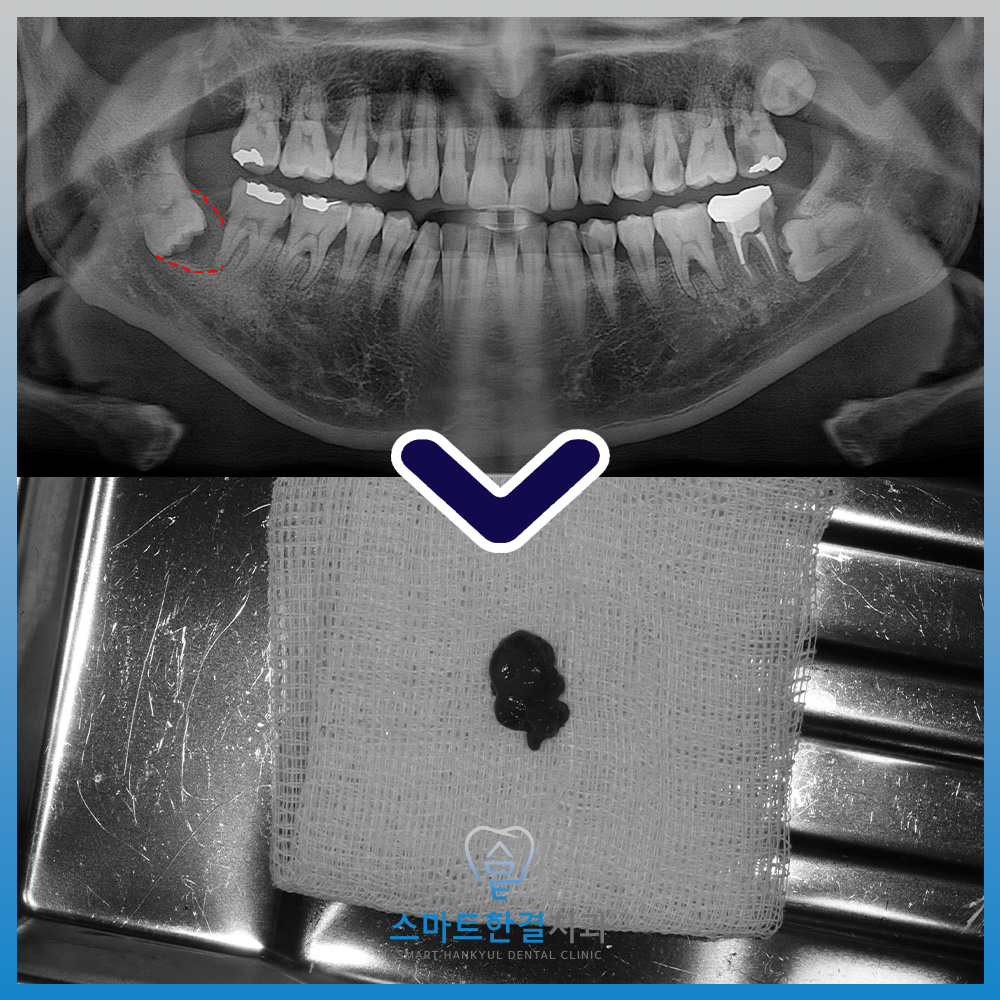

<사랑니 발치 및 낭종적출술 완료>

사랑니 발치를 위해 잇몸을 절개한 뒤,

치아를 분할하면서 주변 조직 손상을 줄이는 방향으로

매복 사랑니를 조심스럽게 제거했어요.

이후 사랑니 주변에 형성되어 있던

낭종 조직도 함께 확인하여,

병변을 깨끗하게 분리한 뒤

낭종적출술을 시행했습니다.

발치 과정 전반에서 신경과의 위치 관계를

충분히 고려해 진행하였으며,

신경 손상 없이 안정적으로

마무리할 수 있었답니다. (^^)